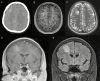

Ependymomas are rare primary central nervous system (CNS) tumors in adults. They occur most commonly in the spinal cord, and have classically been graded histologically into World Health Organization (WHO) grades I, II, or III based on the level of anaplasia. Recent data are showing that genetic heterogeneity occurs within the same histological subgroup and that ependymomas arising from different CNS locations have different molecular signatures. This has renewed interest in developing targeting therapies based on molecular profiles especially given the variable outcomes with radiation and the poor results with cytotoxic agents. In this paper, we present the case of a 46-year-old woman with a classic presentation of spinal cord ependymoma and discuss the current histopathological and molecular classification for ependymomas as well as current guidelines for patient management.